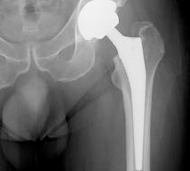

The x-rays below show what cemented, un-cemented and hybrid hip replacements look like.You can also see how the surgeon can measure the patients leg length post operatively on the hybrid x-ray.

CEMENTED:

The Exeter hip was first implanted in 1969 and is one of the most successful cemented hip implants to date. The stem is held in place with cement (polymethylmethacrylate). The stem itself acts like a wedge which pushes into the cement for a tight fit. A plastic hip socket is usually cemented in place.